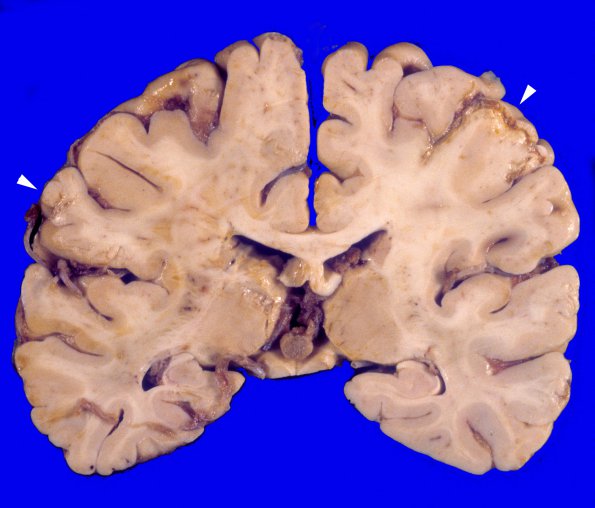

Infarct - Embolic

Several resolving infarcts involve right and left MCA territories.